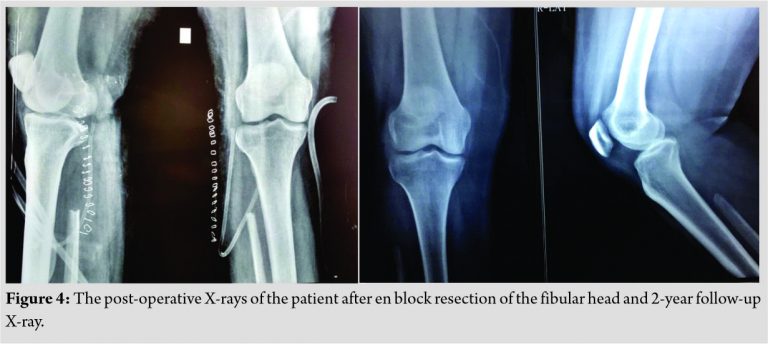

Giant cells are noted in the periphery of the lesion. There was no evidence of calcification. With a suspicion for chondroblastoma, S-100 and epithelial markers were done which all came out to be negative establishing the diagnosis of CMF by exclusion. Although myxoid element was not much evident on histology considering the tumor to be in the earlier stages of evolution diagnosed, early diagnosis of CMF was made. Postoperatively, the patient was put on partial weight-bearing for initial 2 weeks and later resumed full weight-bearing by 4 weeks. The case was followed up for 2 years without any recurrence till date as shown in (Fig. 4)